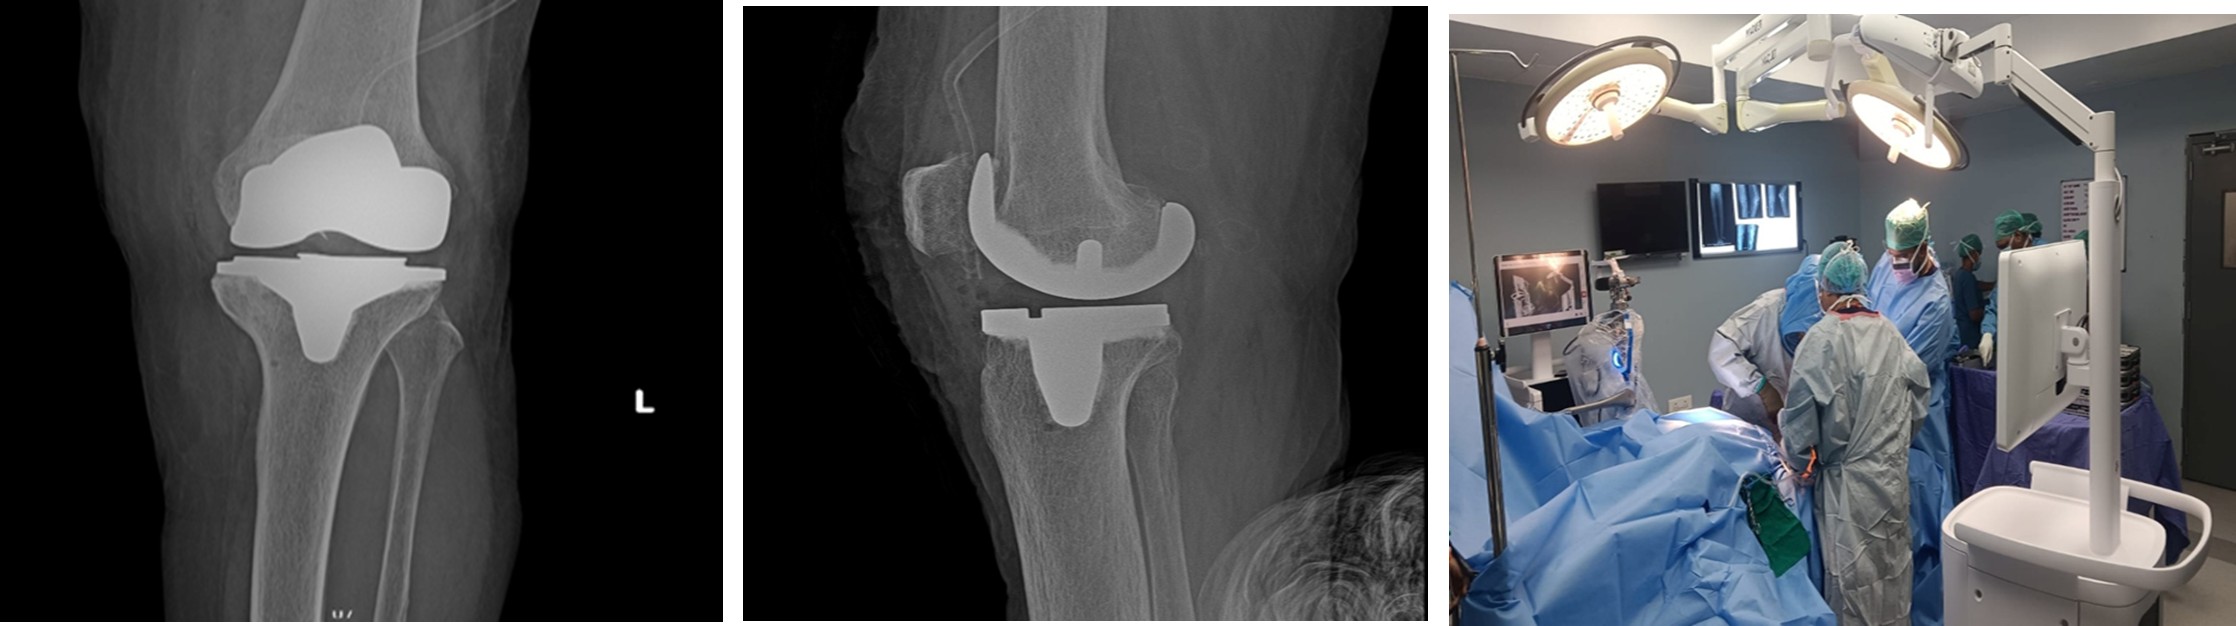

Fig (1): Pre-operation

Fig (2): Post-operation